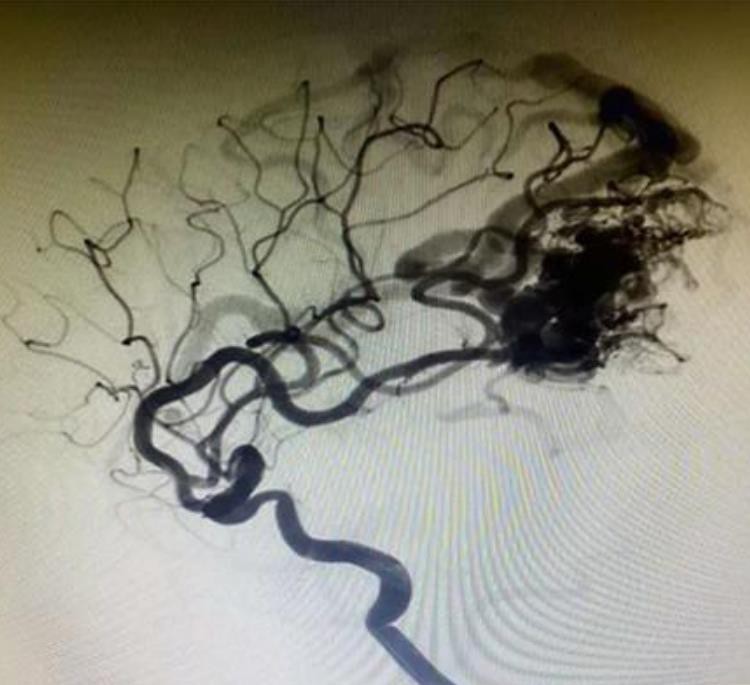

Quan lavaTmAneurismes intracranials El sistema embòlic líquid està en contacte amb la sang o qualsevol solució aquosa, la seva superfície es solidificarà immediatament i formarà una pel·lícula protectora. El DMSO de l’agent embòlic es dilueix i es difon a la sang, de manera que la pols de tàntal embolicat per EVOH es precipita i es solidifica des de l’exterior fins a l’interior. Al mateix temps, la lava es difon fins a la pressió d'injecció. Finalment, forma un cos embòlic esponjós en la posició d’embolització.

Té una millor dispersió i penetració. i pot penetrar profundament en la lesió i arribar al vaixell distal.

La pols de tàntal és més fina, més lentament precipiten i amb més claredat la radiografia en comparació amb els competidors.